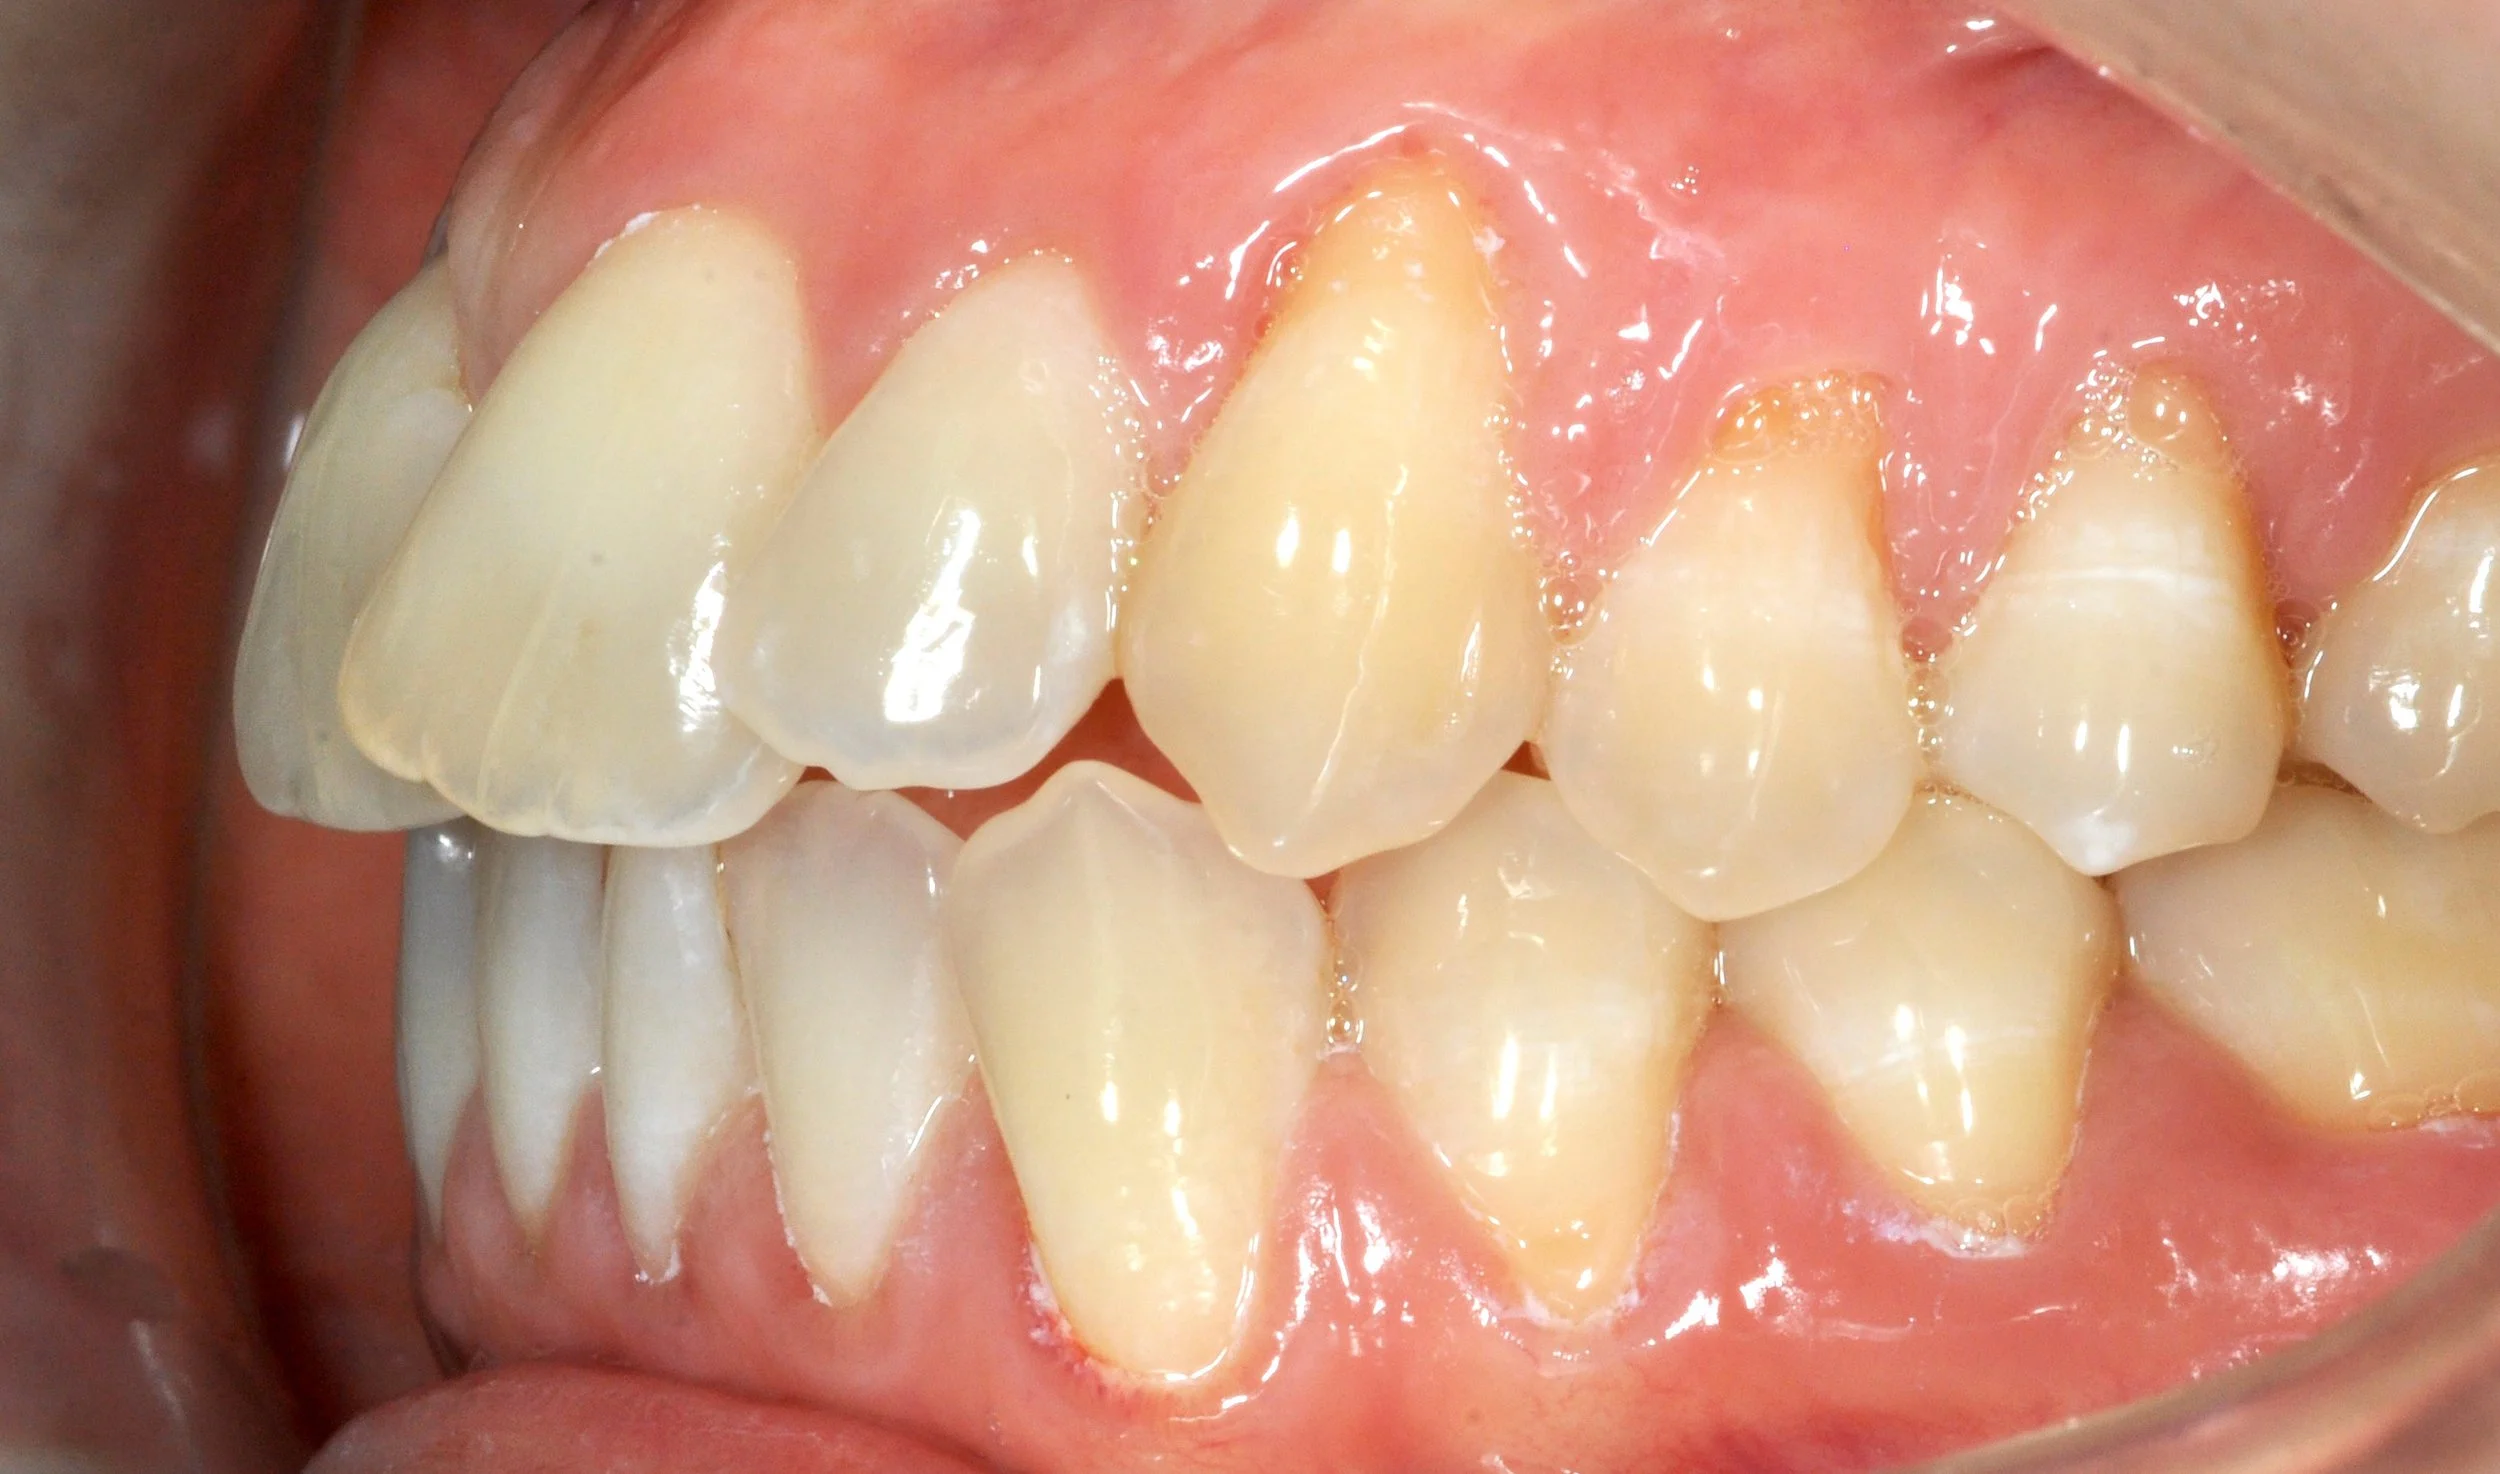

Paziente adulto con incisivi malposizionati e recessioni gengivali, con esposizione della radice e disagio estetico.

Il caso è stato gestito con un approccio multidisciplinare, in stretta collaborazione con il parodontologo: prima è stata corretta la posizione dei denti mediante allineatori trasparenti, creando le condizioni ideali per la salute gengivale; successivamente le recessioni sono state trattate con un intervento mucogengivale.

Il lavoro di team ha permesso di ottenere un risultato armonioso, stabile e attento non solo all’estetica, ma soprattutto alla salute a lungo termine.

PRIMA